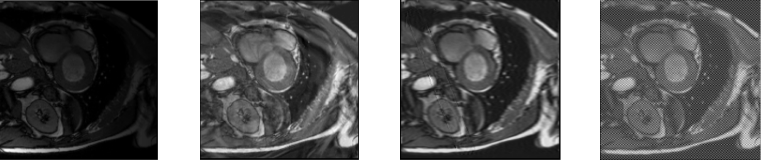

Refer to caption

Figure 1: Examples of original and augmented images produced by the pipeline on cardiac data.

For our framework, we randomly mix an input batch b with fractal images, along with randomly augmenting the input batch with different, traditional augmentations t. So, a batch after mixing is characterized by: b+=mix(t(b))superscript𝑏𝑚𝑖𝑥𝑡𝑏b^{+}=mix(t(b)), where mix can be additive or multiplicative functions between the fractal image and the image slice. We empirically found through our experiments that mixing intensity should not be too high, so that semantic content can be preserved and that the augmentation should not be applied across the entire training and only through controlled settings. Otherwise, the adversarial training will lead to the creation of highly corrupted images and the backpropagation algorithm will echo the effect. We present some image examples in Figure 1.